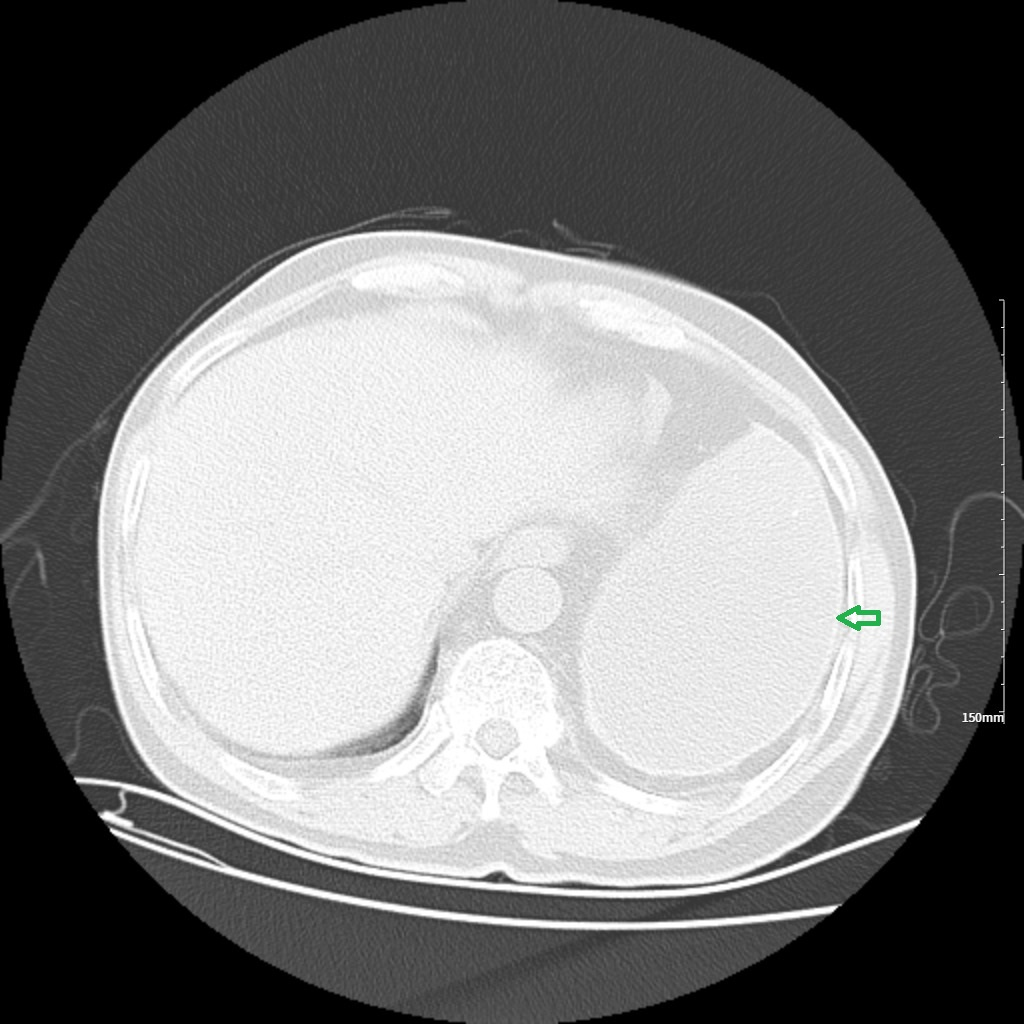

胸部CT示两肺及肋骨平扫未见明显挫伤征象,左侧胸腔包裹性积液并胸膜增厚、钙化,左肺不张(见图1-图4)。

3. 绿色箭头:左侧胸腔积液。